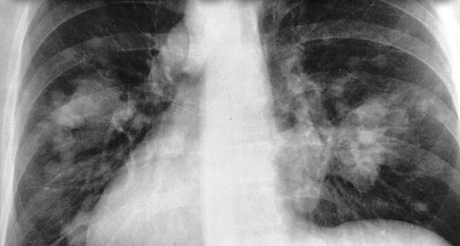

7 million premature deaths annually linked to air pollution[edit]

25 March, 2014 – In new estimates released today, WHO reports that in 2012 around 7 million people died – one in eight of total global deaths – as a result of air pollution exposure. This finding more than doubles previous estimates and confirms that air pollution is now the world’s largest single environmental health risk. Reducing air pollution could save millions of lives.